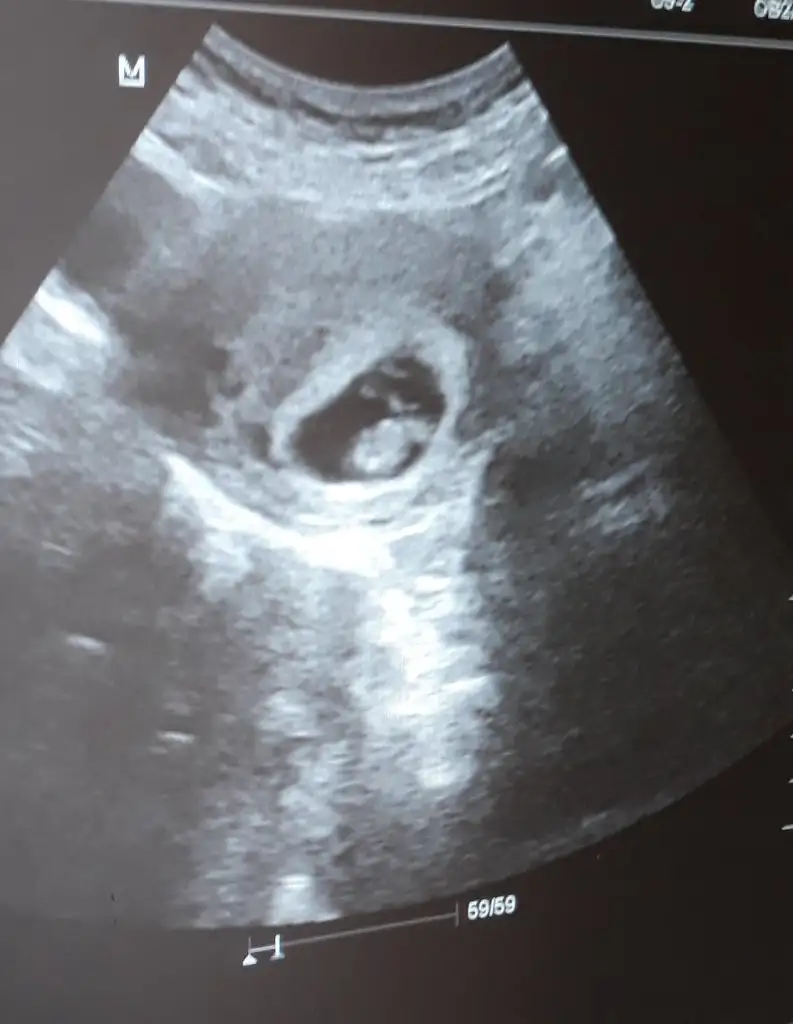

Karından ultrason 4+4 haftalık ramzi teorisine göre bakarmısınız cinsiyetineRamzi teorisine göre ( bilimsel bir araştırma sonucuymuş ve %85 doğruluğu varmış). İlk 6-8 haftalık ultrason görüntüsüne göre bebeğin kesenin içersinde soldan ya da sağdan girişine göre cinsiyet tahmini yapılıyor. Bilimsel olunca tecrübeli annelerimiz yada anne adaylarımızdan yardım istiyoruz. Doğruluğu var mı öğrenmek adına :) Bizleri aydınlatırsanız çok seviniriz. bu teorieye göre;

Vajinal muayeneyle bakıldıysa eğer;

Sağdan girmiş gözüküyosa aslında solmuş ve ERKEK,

Soldan girmiş gözüküyosa aslında sağmış ve KIZ ,

Karından bakıldıysa eğer,

Soldan girmiş gözüküyosa gerçektede solmuş ve ERKEK,

Sağdan girmiş gözüküyosa gerçekte de sağmış ve KIZ,

4+4 haftalık burda cinsiyeti nedir ramzi teorisine göreRamzi teorisine göre ( bilimsel bir araştırma sonucuymuş ve %85 doğruluğu varmış). İlk 6-8 haftalık ultrason görüntüsüne göre bebeğin kesenin içersinde soldan ya da sağdan girişine göre cinsiyet tahmini yapılıyor. Bilimsel olunca tecrübeli annelerimiz yada anne adaylarımızdan yardım istiyoruz. Doğruluğu var mı öğrenmek adına :) Bizleri aydınlatırsanız çok seviniriz. bu teorieye göre;